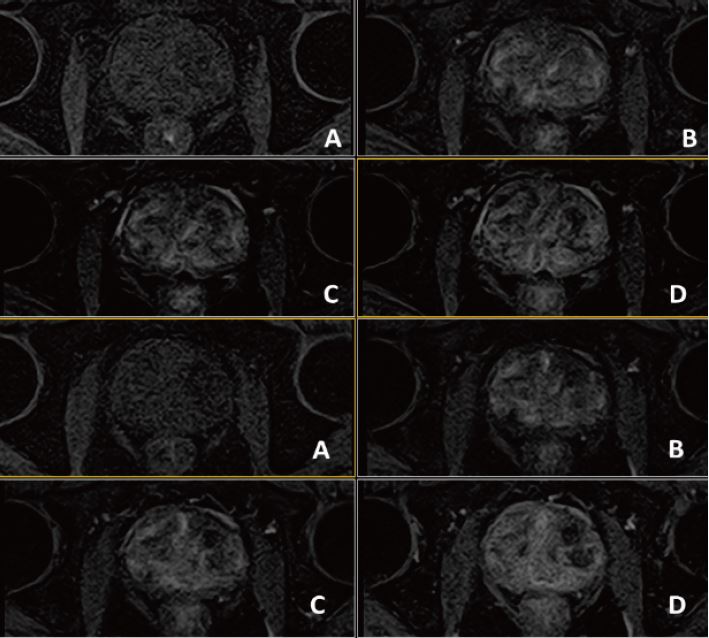

Рис. 3. Аксиальне DWI – A=b0, B=Iso b800, C=Iso b1000 e, D=Iso ADC (за протоколом mpMR)

Рис. 4. Динаміка. Аксіал (12 фаз) : A=1a phase pre, B=3a phase pos, C=6a phase pos, D=12a phase (згідно протоколу m pMR)

Рис. 7. Аксіальне DWI – A=b0, B=Iso b800, C=Iso b1000 e, D=Iso ADC (за протоколом mpMR)

Рис. 8. Динаміка. Аксіал (12 фаз): A=1a phase pre, B=3a phase pos, C=6a phase pos, D=12a phase (за протоколом mpMR) .

Рис. 11. Аксіальне DWI – A=b0, B=Iso b800, C=Iso b1000 e, D=Iso ADC (за протоколом mpMR).

Рис. 12. Динаміка. Аксіал (12 фаз) : A=1a phase pre, B=3a phase pos, C=6a phase pos, D=12a phase (згідно протоколу m pMR)

Рис. 15. Aксіальне DWI – A=b0, B=Iso b800, C=Iso b1000 e, D=Iso ADC (за протоколом mpMR)

Рис. 16.  Динаіка. Аксіал (12 фаз)– A=1a phase pre, B=3a phase pos, C=6a phase pos, D=12a phase (за протоколом mpRM).